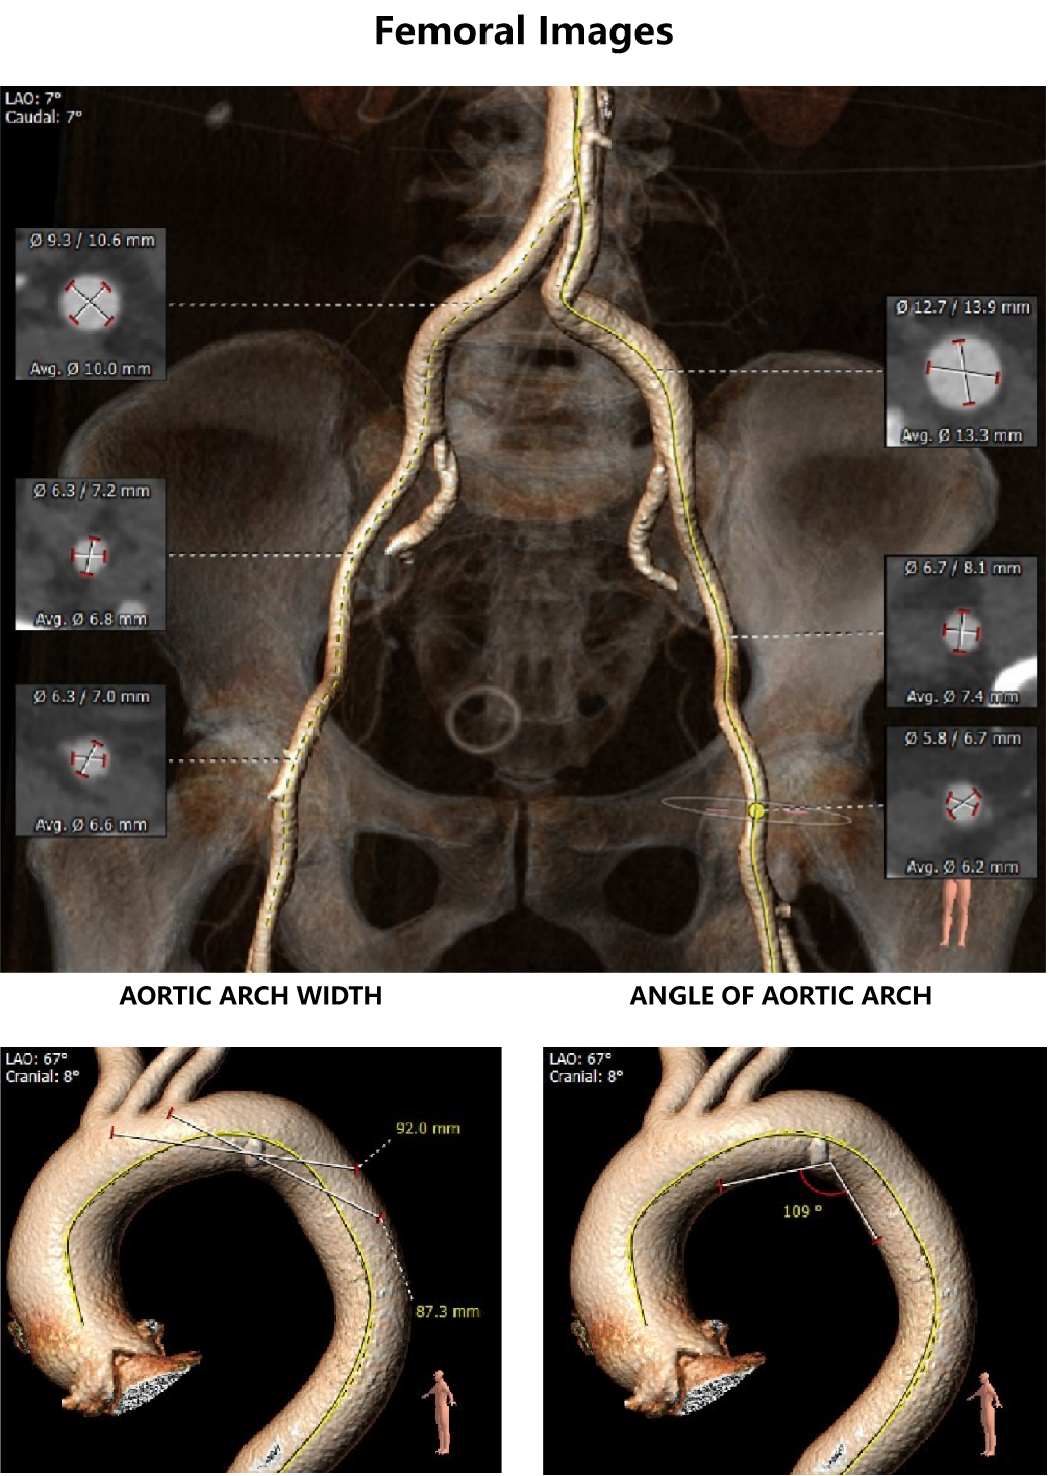

外周血管及主动脉弓解剖:

患者主动脉弓角度、弓距可。双侧入路血管内径可,CT见明显钙化,股动脉分叉位置可,右侧股动脉存在钙化斑块,存在血管损伤风险。

入路血管无严重钙化及其他病变,双侧血管内径良好,整体入路血管条件良好。